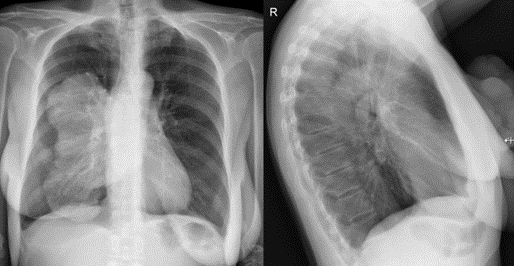

Анатомические изображения сегментов легких различных животных

Раздел: Другие животные